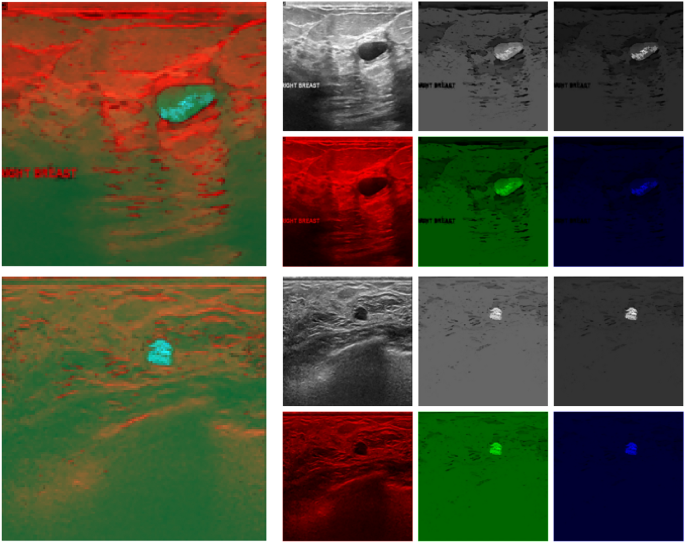

Illustration of hybrid pseudo-color images. In each of the two cases, the hybrid image is shown on the left, and its components are on the right (left to right: the original US image and two fuzzy connectivity scenes (\({\textbf {W}}_{1}\) and \({\textbf {W}}_{2}\), respectively) as grayscale images above, and mapped to the appropriate chromatic channel below).

The \({\textbf {W}}_{1}\) vector emphasizes mean intensity-related similarity, while \({\textbf {W}}_{2}\) favors gradient similarity. The fuzzy scenes they produce carry different information. Both are combined with the original US scan to the pseudo-RGB image (Fig. 3) and passed as an input to the CNN-based main segmentation stage.